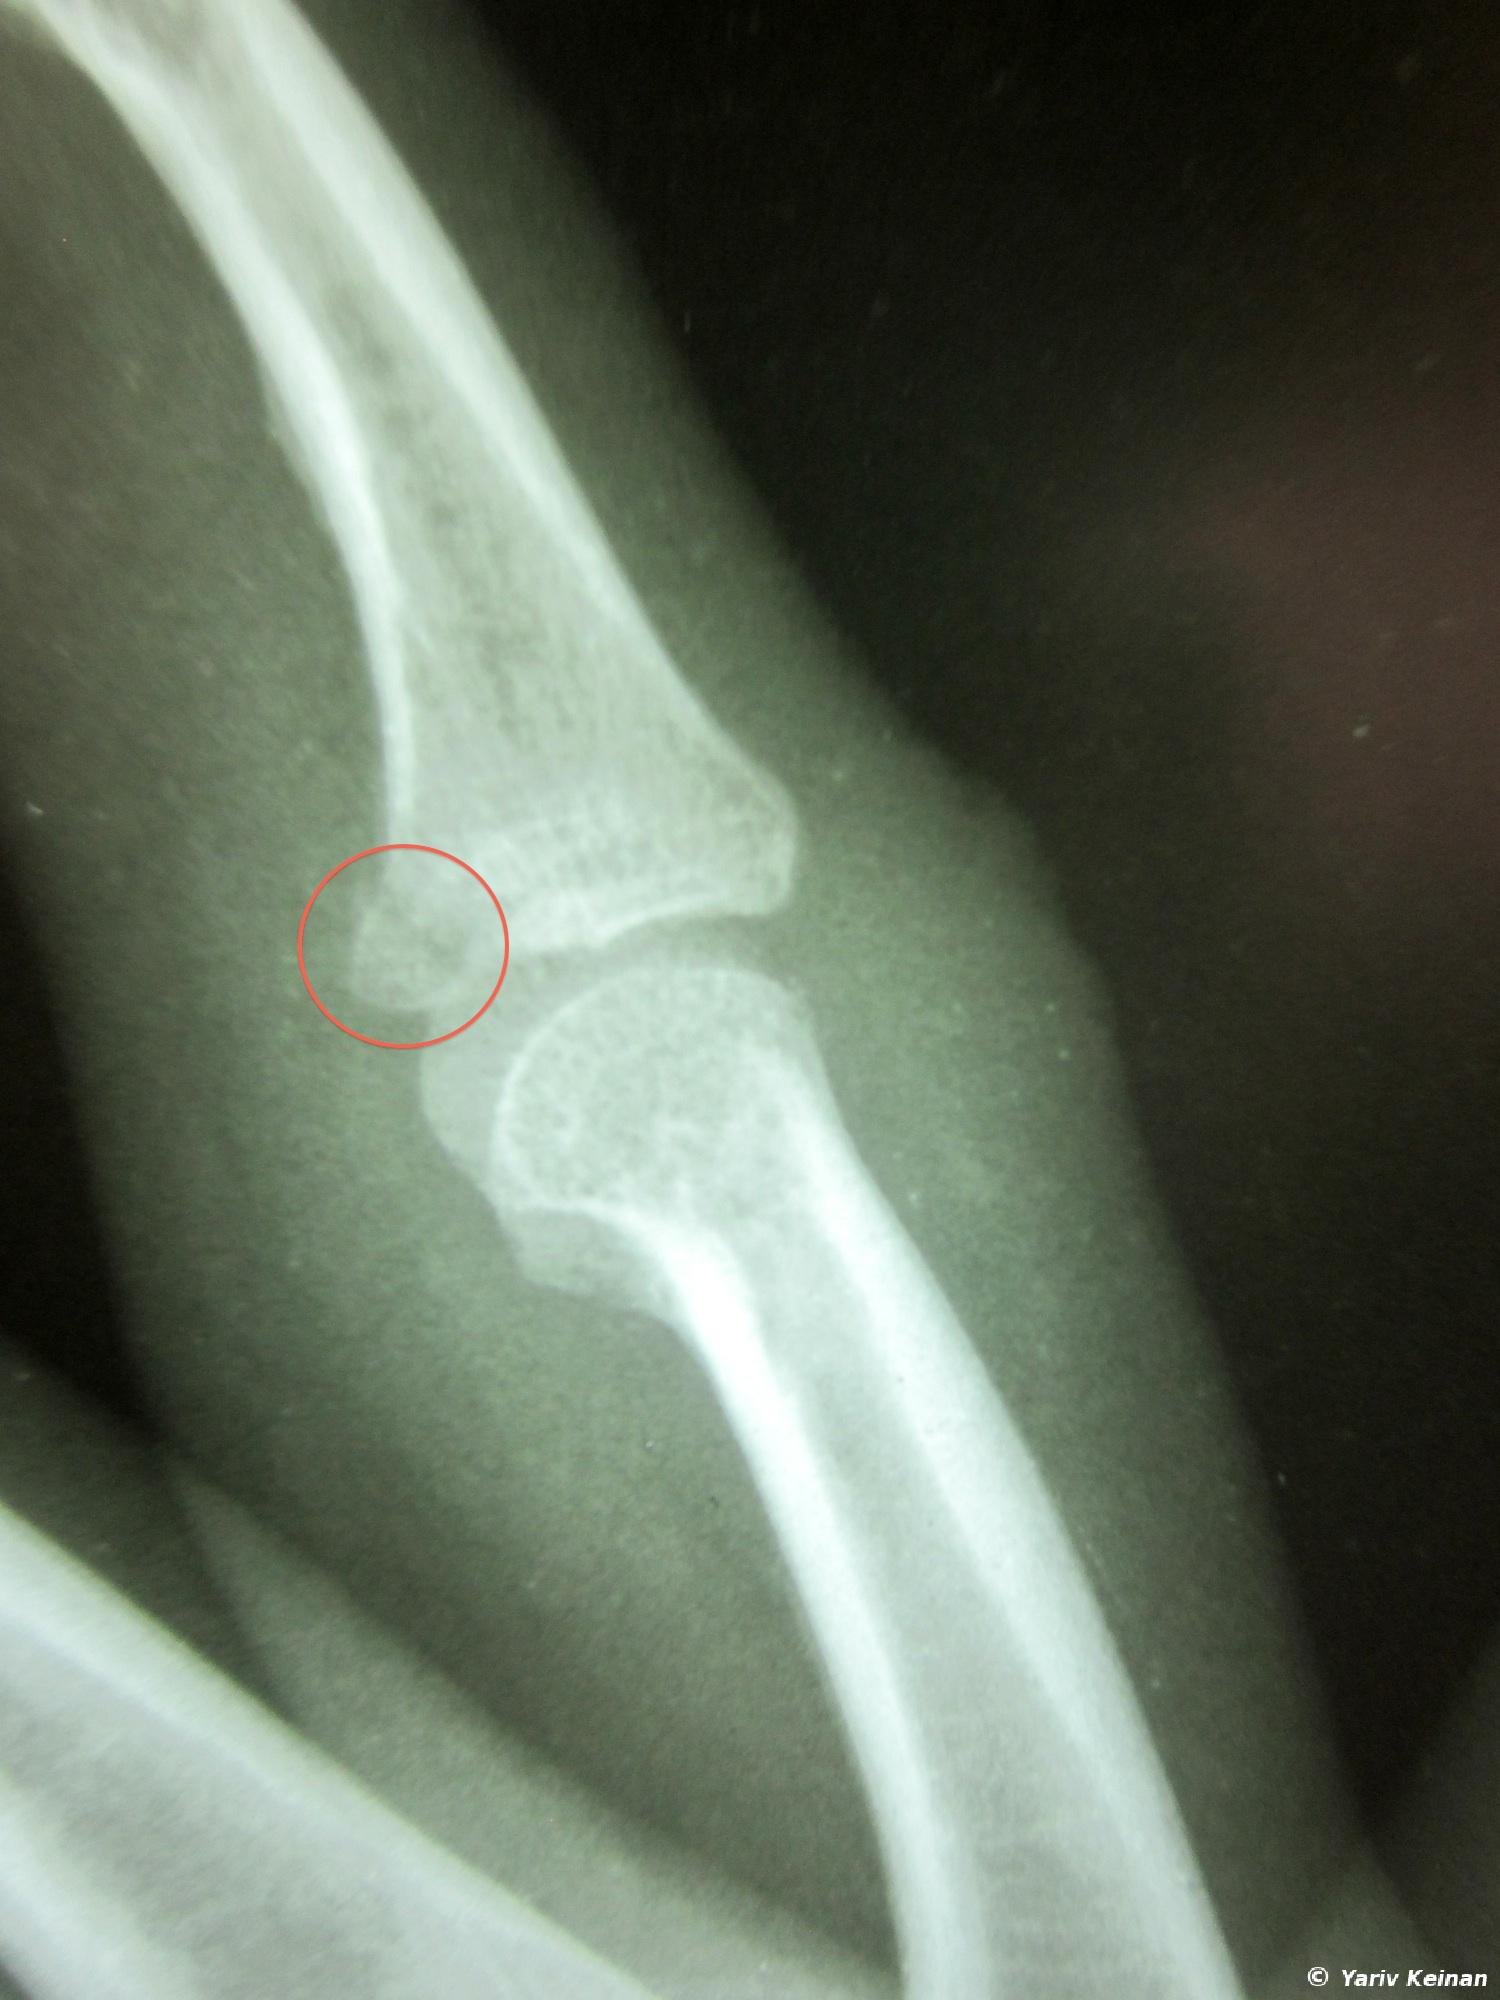

So now I am back in Thailand after a smooth border crossing this morning and a short ride to Chiang Rai. I like this town, it has a really nice vibe in the backpackers area. Once here I went on a different type of experience – the hospital experience. I tripped over some steps back in Vientiane over 2 weeks ago and hurt my ring figure. It wasn’t so bad but then I tripped again during the jungle track in Luang Nam Tha and it got a bit worse. Since there are no decent hospitals in the entire country of Laos anyway (not to mention the north) I decided to just make a ghetto splint from a popsicle stick and have it examined in Thailand. Mind you that it didn’t hurt much and I was able to easily ride a motorcycle for 2 days AND zip-line through the jungle safely, but it was better to have it looked at by a doctor. I thought I just tore or hurt a ligament but it turned out that I actually fractured the middle bone of my right ring finger.

So now I have this huge thing on my hand for 4 weeks even though there is hardly any pain (unless I flex my finger all the way) and I feel very ridiculous. Oh well. BTW, the bill for the medical treatment was:

– X-Ray